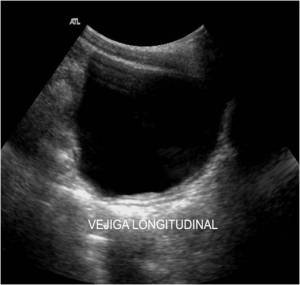

Bien, bajando por la Línea Alba, una vez entramos en la pelvis menor nos vamos a encontrar con una estructura redonda, anecoica que visualizaremos dependiendo de la replección que tenga.

Técnicamente la vejiga tiene un acceso fácil, la localizaremos por encima del pubis. Debemos realizar cortes transverso y longitudinal y observar minuciosamente las paredes de la estructura, por eso debe estar bien repleccionada.

Ecográficamente vamos a ver una estructura Anecoica, de bordes lisos, como un globo. Una replección exagerada puede dar lugar a artefactos indeseados y estudios no valorables.